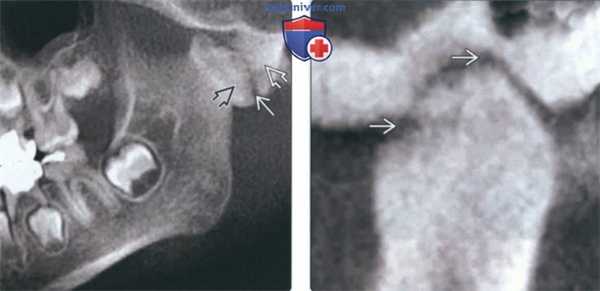

(Слева) На панорамной реформатированной КЛКТ у восьмилетней девочки с фиброзным анкилозом вследствие травмы и подмыщелкового перелома со смещением определяются крупные костные включения, сращенные с височной костью и нижней челюстью. Между включениями костной ткани определяется просветление, представляющее собой сохранившееся суставное пространство.

(Справа) На косой сагиттальной КЛКТ левого ВНЧС у взрослой женщины с фиброзным поствоспалительным анкилозом между мыщелком и суставной ямкой визуализируется суставное пространство в виде тонкого неравномерного просветления.